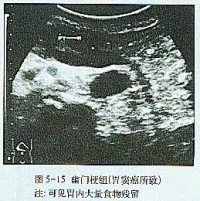

大多起病缓慢,迷走神经切断术者常于术后第2周开始进流质饮食后发病。主要症状有腹胀、上腹或脐周隐痛,恶心和持续性呕吐。呕吐物为混浊的棕绿色或咖啡色液体,呕吐后症状并不减轻。随着病情的加重,全身情况进行性恶化,严重者可出现脱水、碱中毒,并表现为烦躁不安呼吸急促、手足抽搐血压下降和休克。突出的体征为上腹膨胀,可见毫无蠕动的胃轮廓,局部有压痛叩诊过度回响,有振水声。脐右偏上出现局限性包块,外观隆起,触之光滑而有弹性、轻压痛,其右下边界较清,此为极度扩张的胃窦,称“巨胃窦症”,乃是急性胃扩张特有的重要体征,可作为临床诊断的有力佐证。